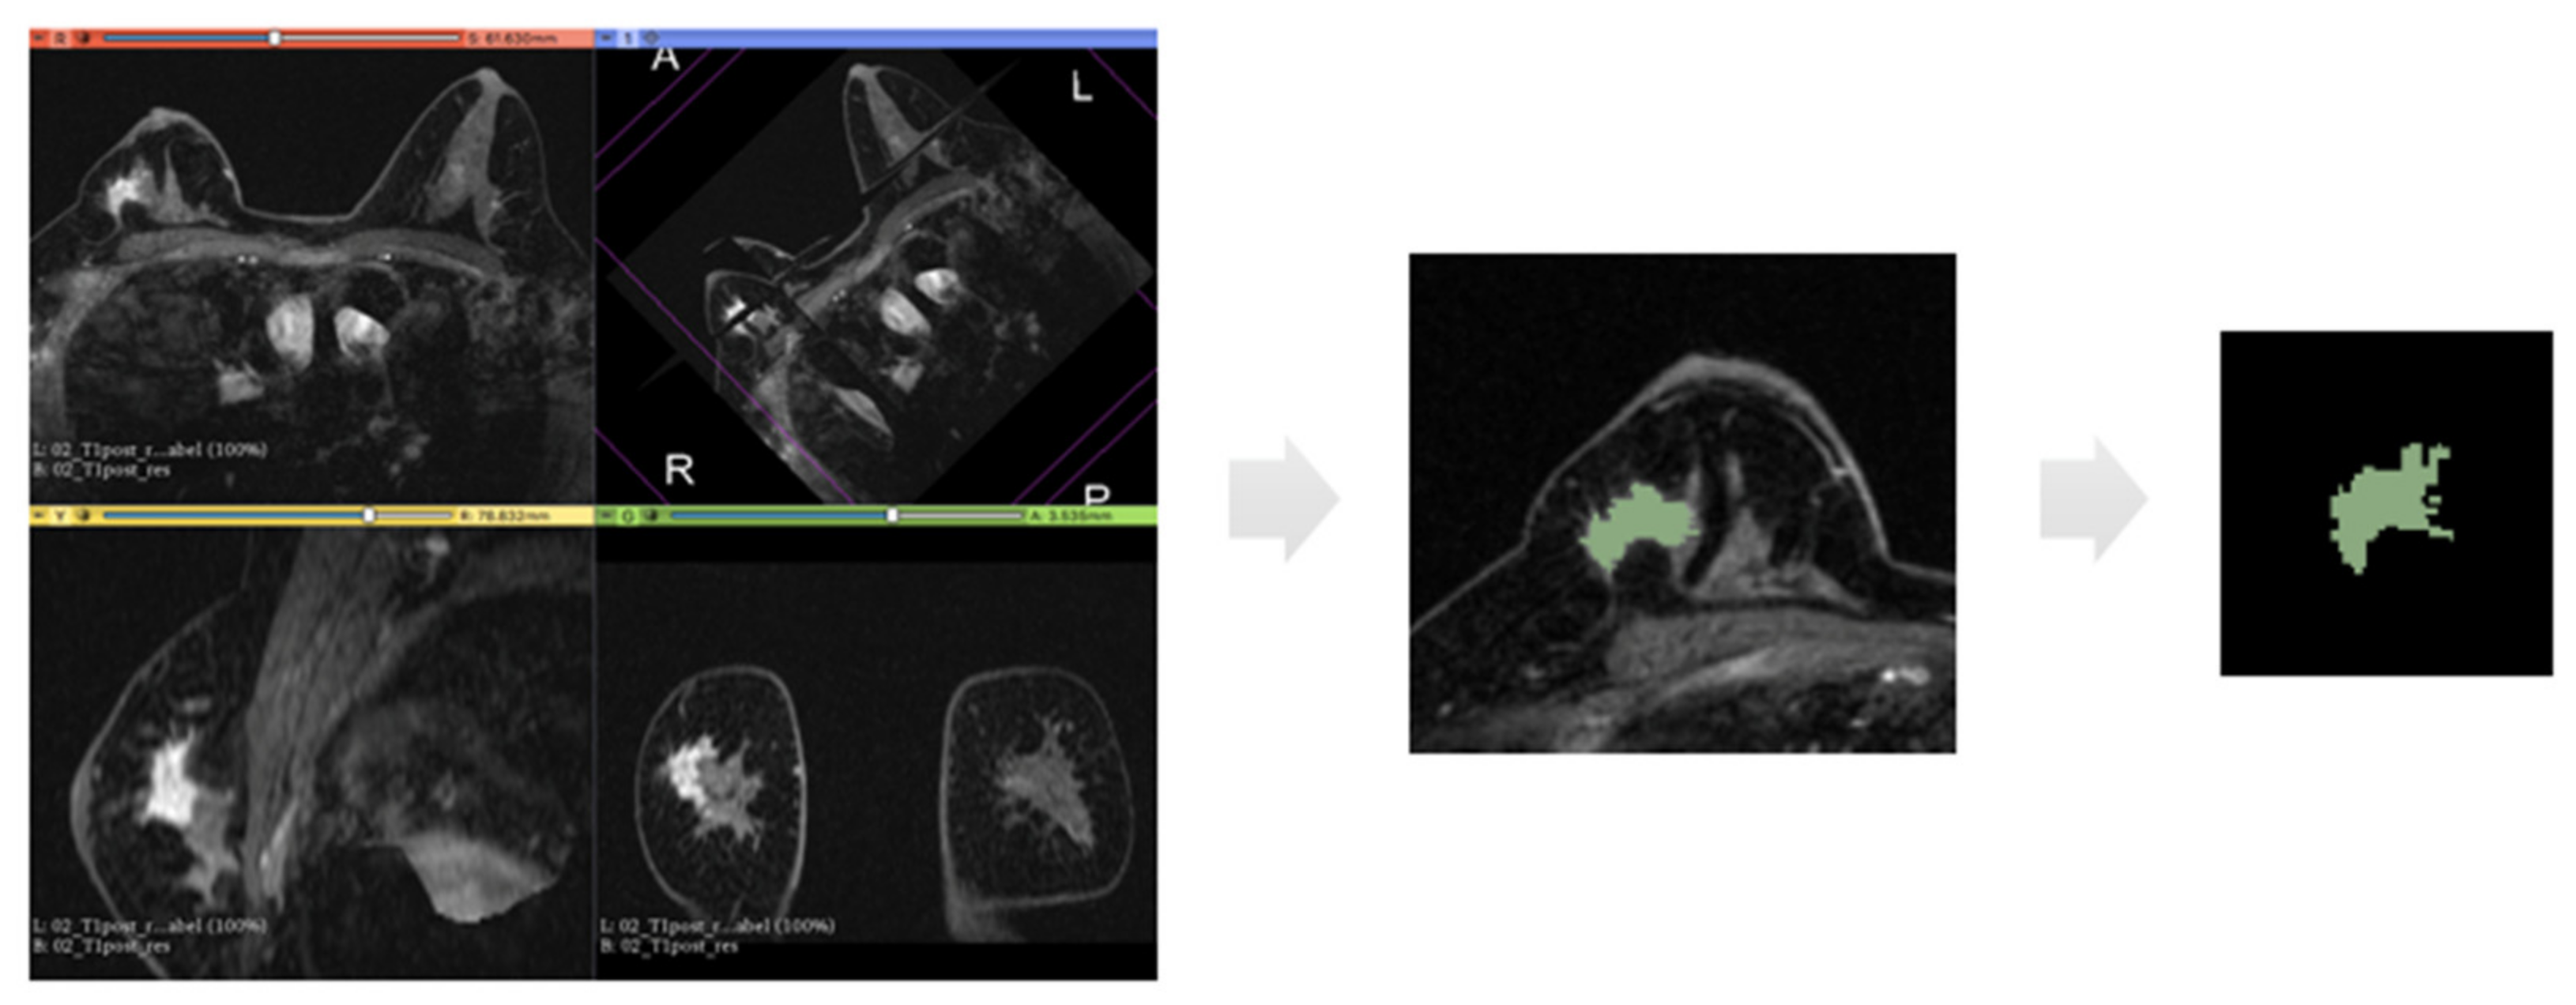

At this point, for each case, a label-map was generated. Using manual and assisted segmentation techniques with the thresholding technique, the lesions were manually drawn (Figure 2).

Figure 2. Representation of the extraction of a segmentation mask. From left to right: first panel represents an example of 3D image analysed in our dataset which is the second phase of subtracted post-contrast sequence; then, for each 2D slice, we have the region of interest drawn around the tumour mass and finally the binary mask extracted from this segmentation.